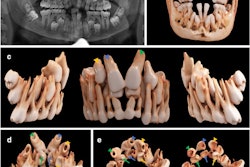

The mesiodens following removal via a maxillary vestibular transnasal approach.